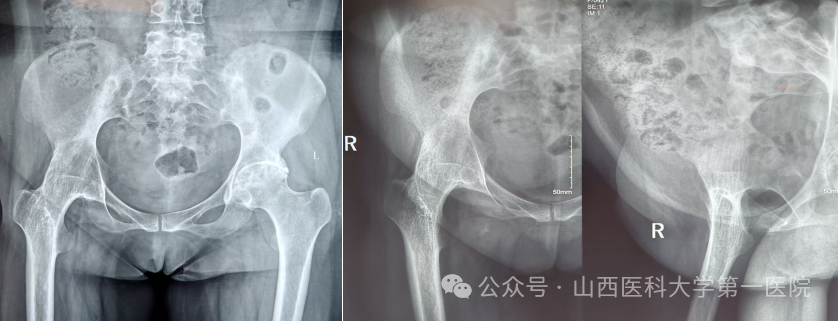

一名42岁的强直性脊柱炎患者,多年来饱受病痛折磨。随着病情进展,双侧髋关节逐渐“锈死”,无法弯腰、下蹲,甚至连坐下都成了奢望——吃饭只能站着,休息只能躺着,生活自理能力几乎丧失。接诊后,骨科杨自权主任团队对患者进行全面检查,发现患者不仅脊柱强直呈“板状腰”,双侧髋关节出现严重融合,而且双膝、双踝关节功能明显下降,手术难度极大。

针对患者复杂病情,科室组织多学科讨论。为实现从“站坐难安”到“稳步前行”,杨自权主任团队决定先为患者实施“右侧人工全髋关节置换术”。术中,团队凭借精湛技术,精准处理强直融合的关节结构,在保护周围神经血管的同时,成功植入新的人工关节假体。

强直性脊柱炎伴髋关节病变的置换手术,被誉为骨科领域的“硬仗”。杨自权总结此类患者三大诊疗难点:一是麻醉困难,患者脊柱强直,常无法配合常规麻醉体位;二是解剖变异,长期炎症导致关节周围骨质疏松、肌肉萎缩,手术视野不清,风险极高;三是对手术精度要求更高,假体安放的位置、角度稍有偏差,就会影响术后关节稳定性及使用寿命。